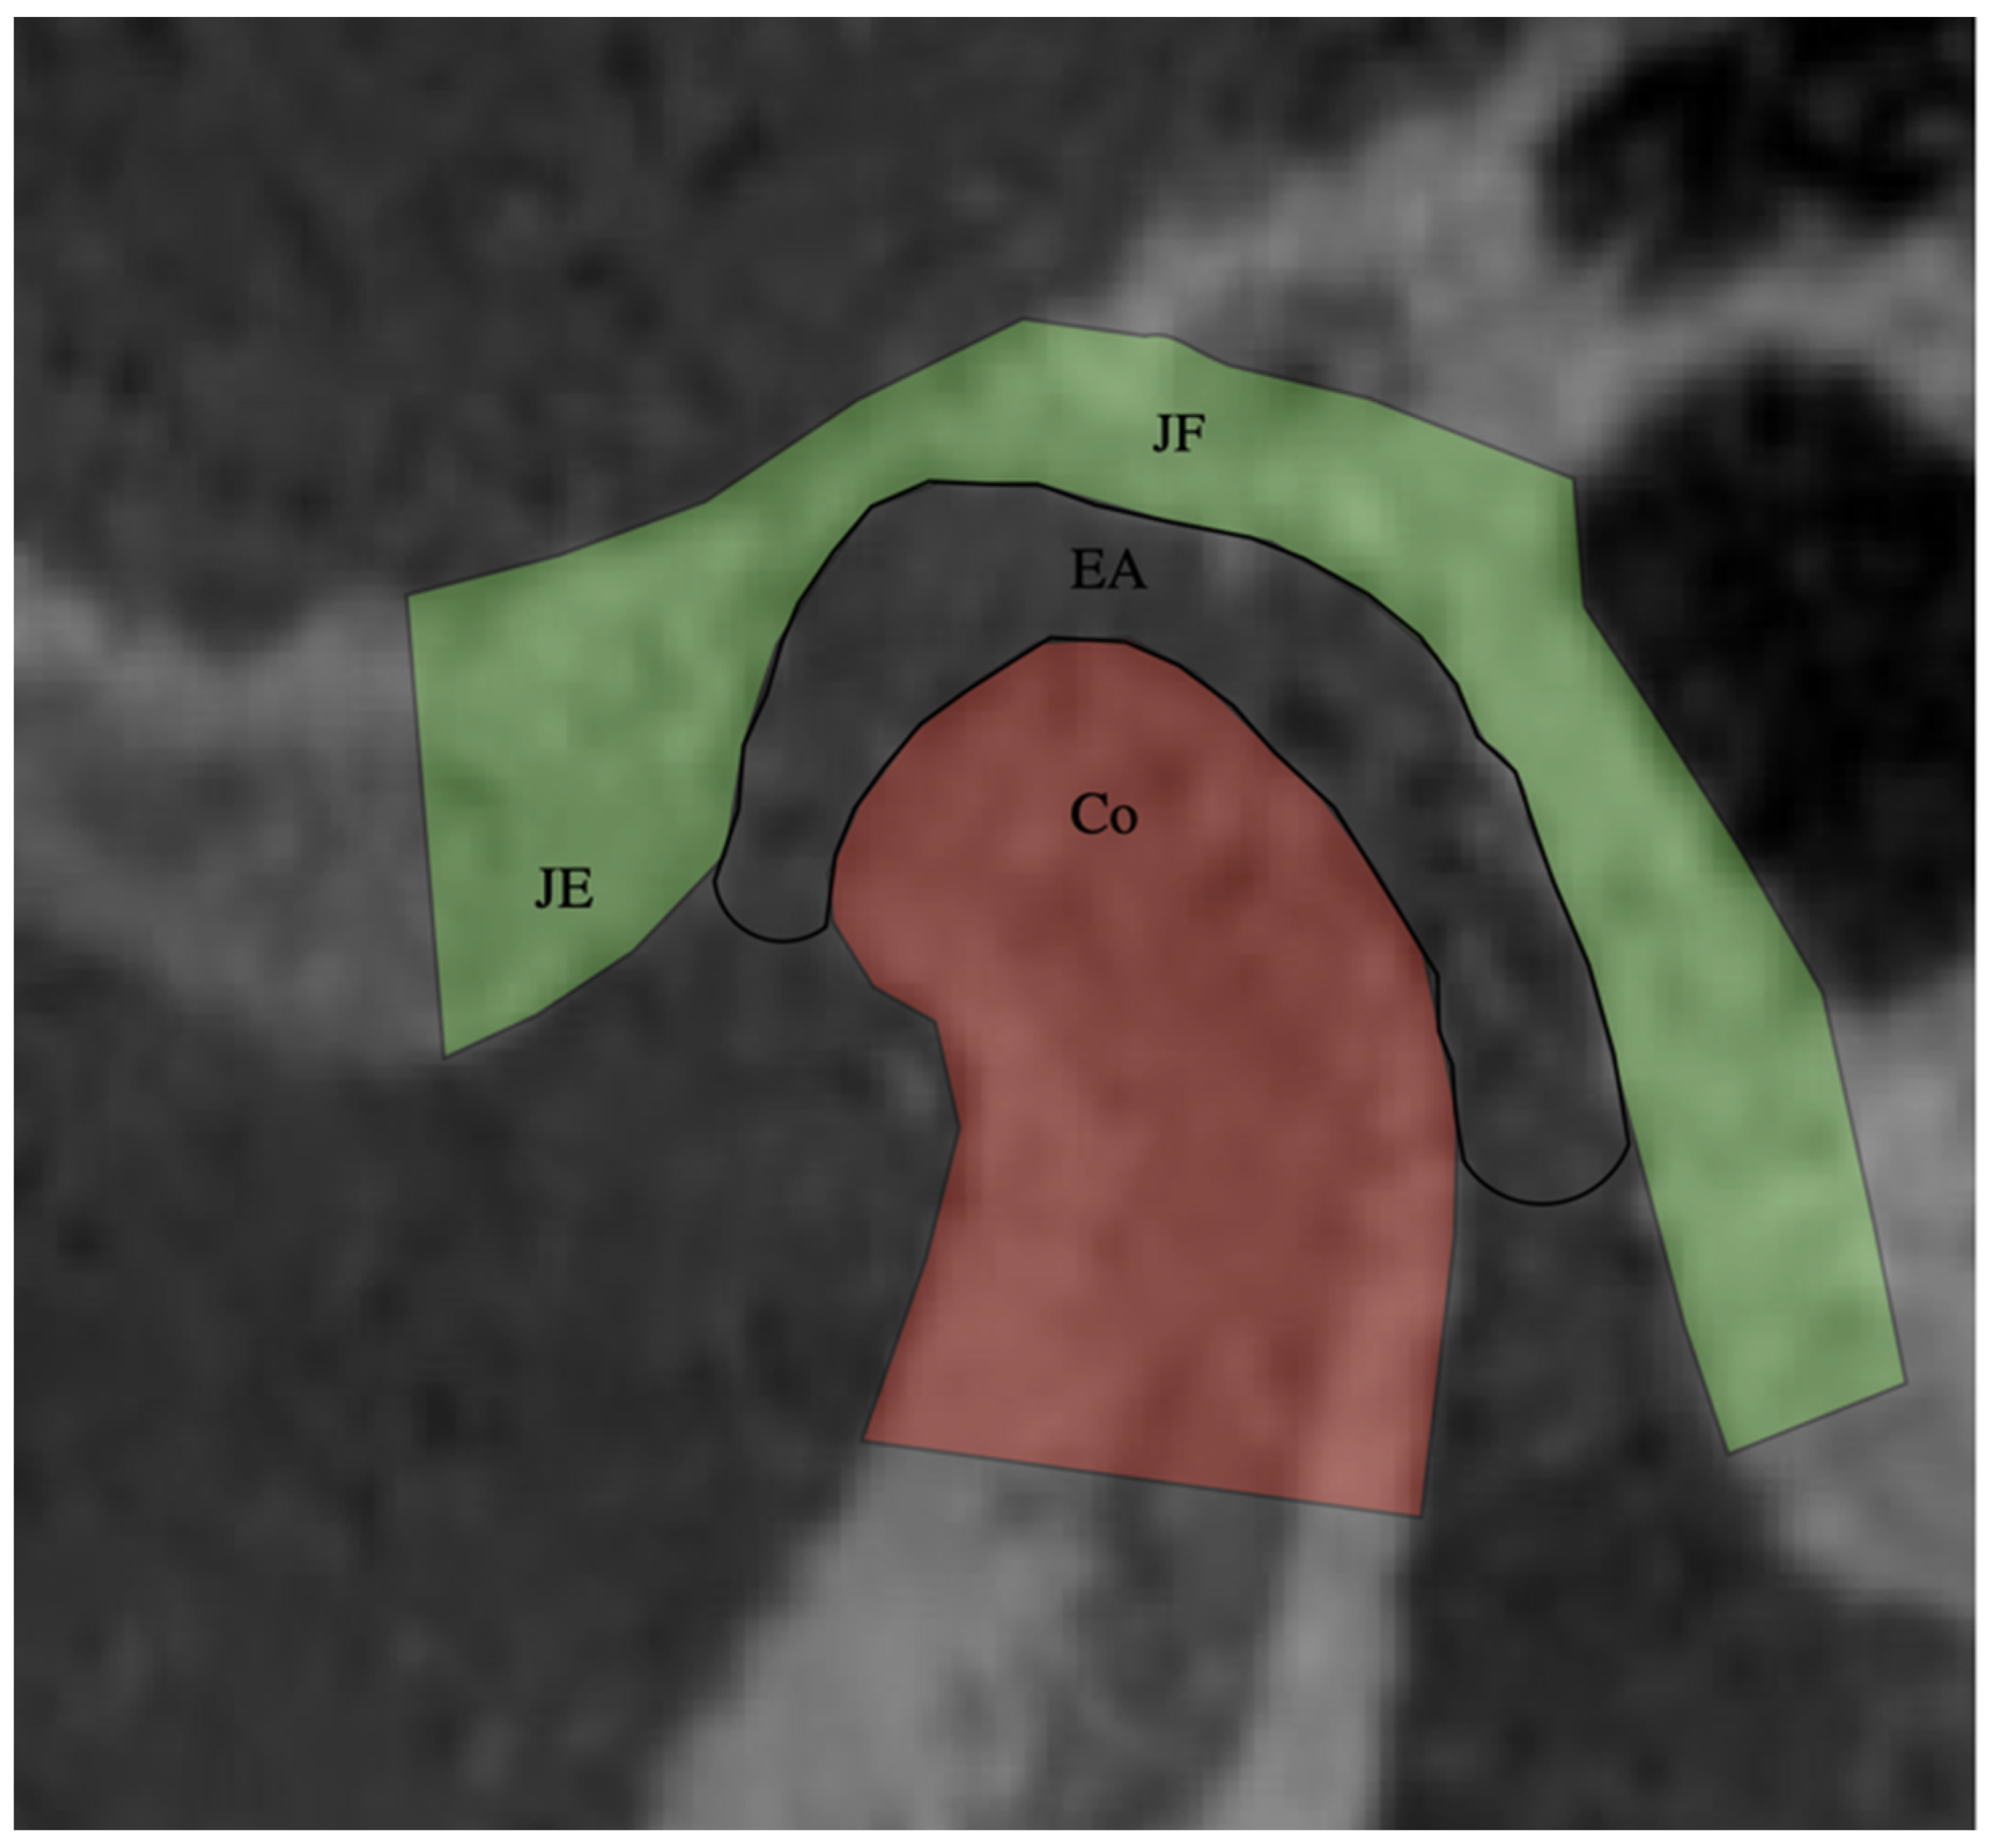

2.3. Joint Space (Sagittal Measurements)

2.4. Joint Space (JS) Average

2.5. Coronal Analysis of the Condyle